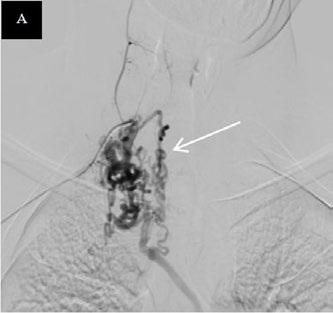

Create a flipbook